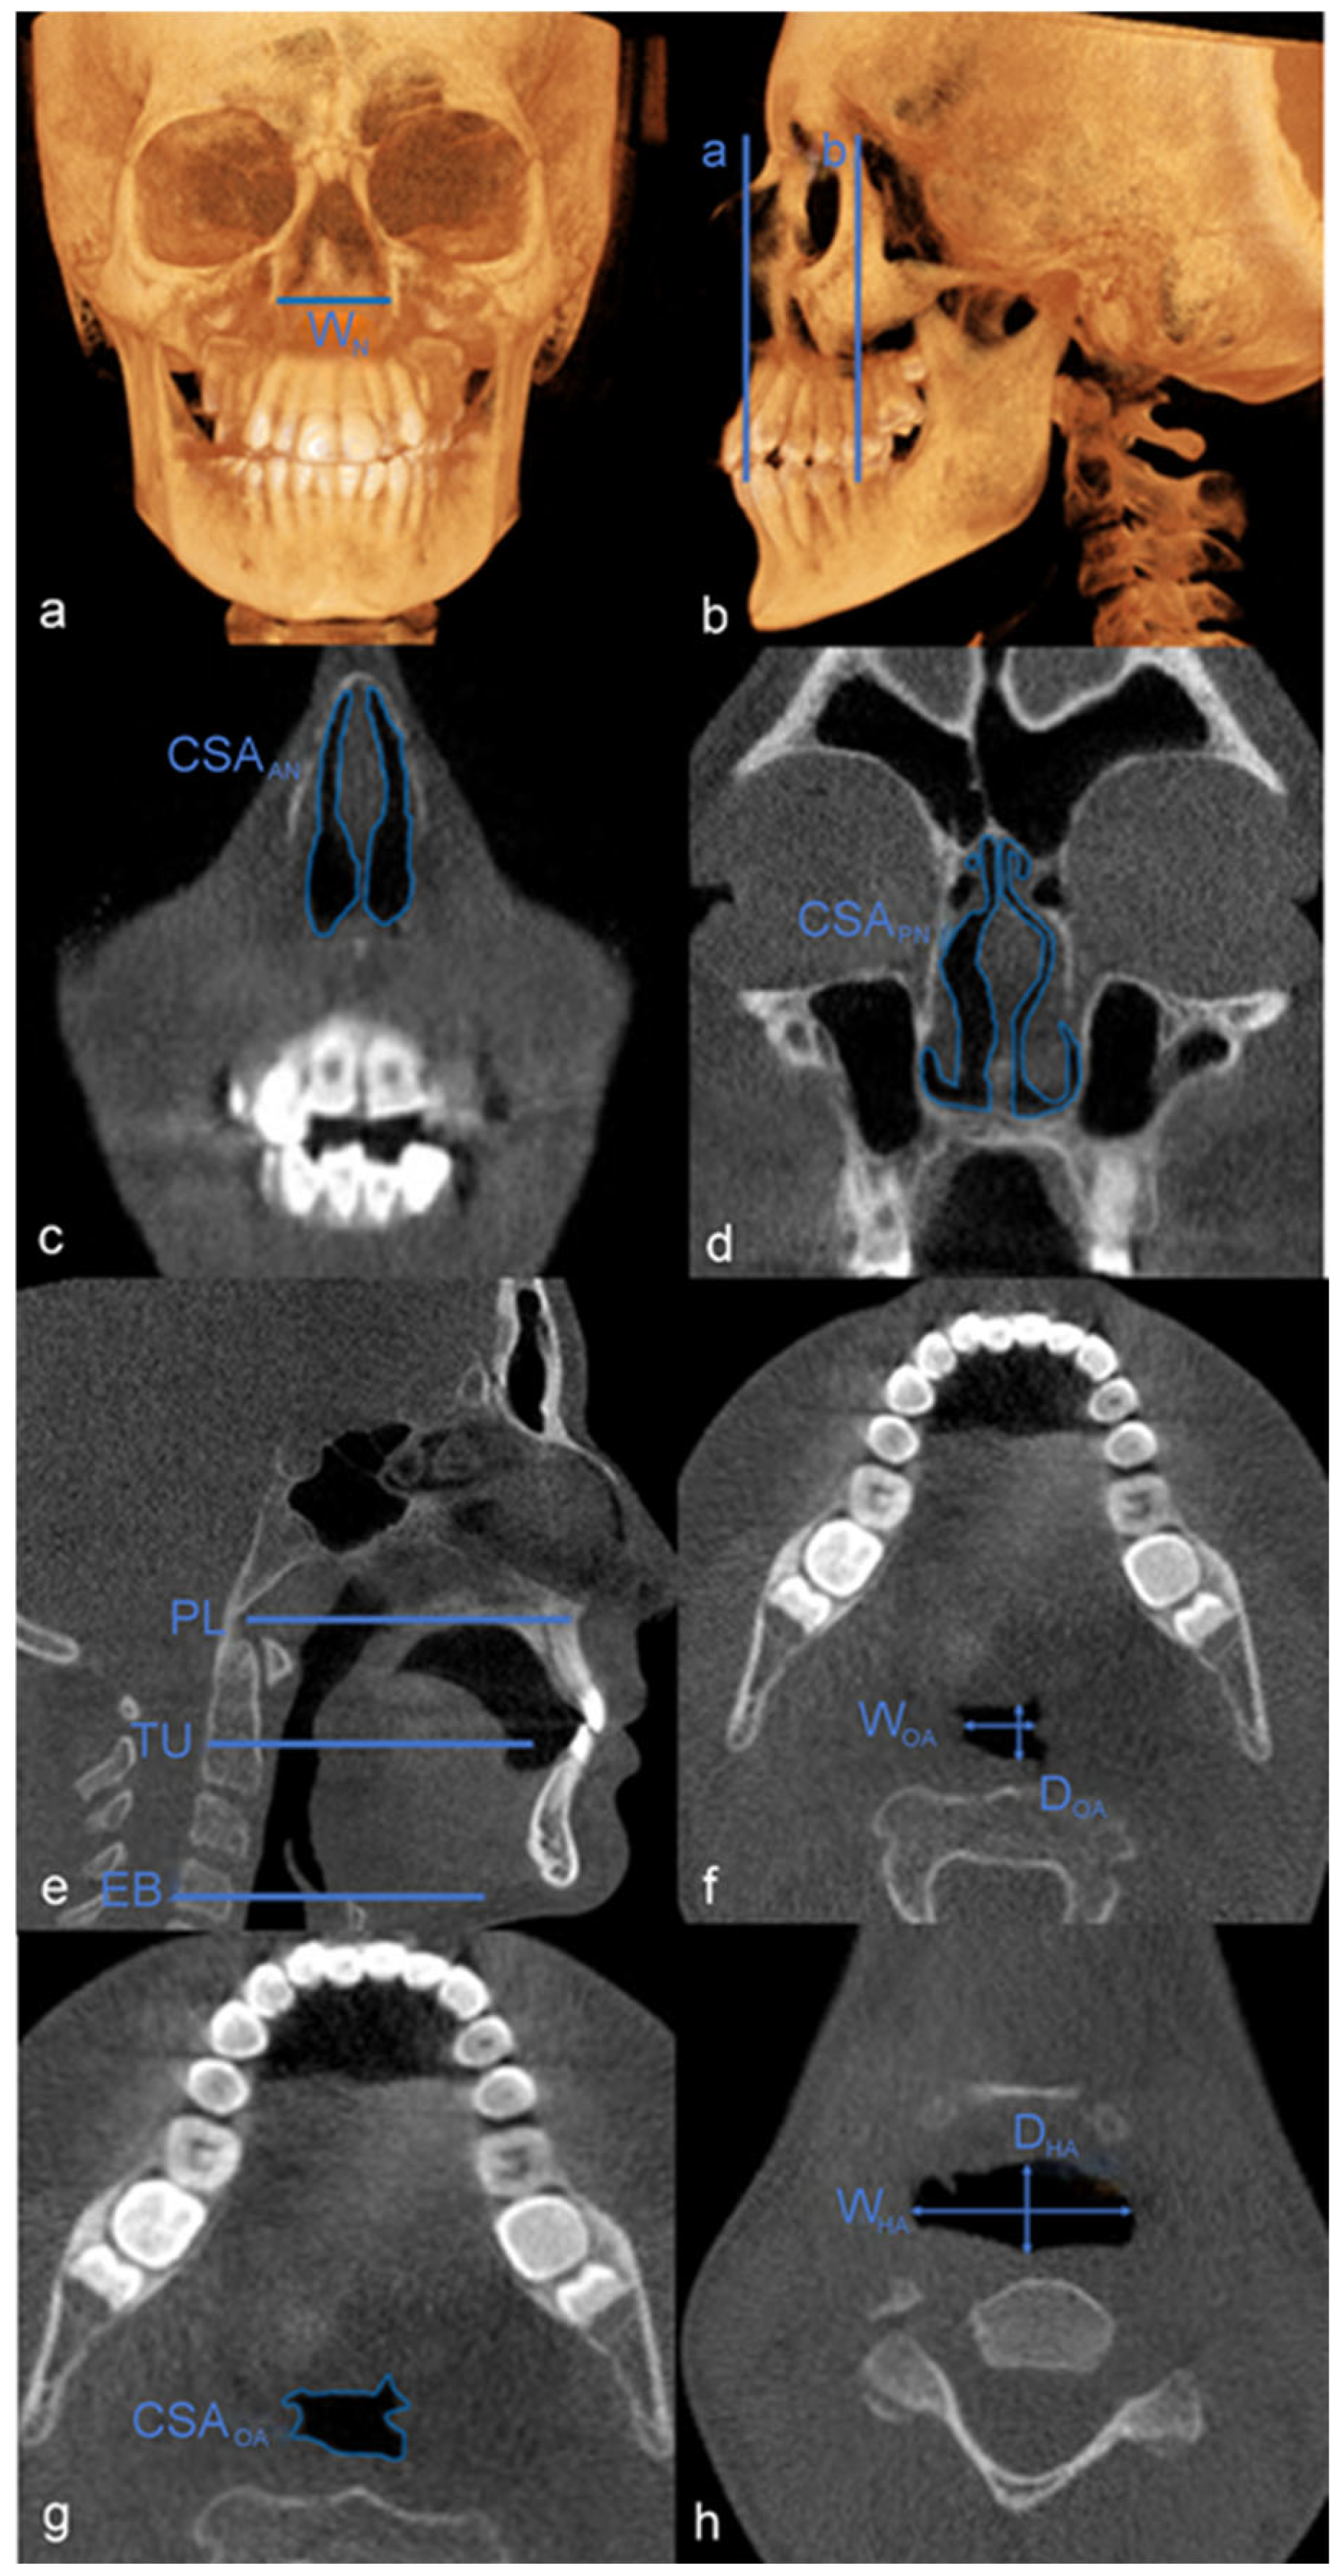

| Abbreviations | Definitions | Descriptions | Images Utilized |

|---|---|---|---|

| S | Sella turcica | Midpoint of the sella turcica | Cephalometric images generated from CBCT |

| N | Nasion | Intersection between the internal and nasofrontal sutures in the midsagittal plane | Cephalometric images generated from CBCT |

| A | A point | Deepest midline point of the premaxilla between the anterior nasal spine and prosthion | Cephalometric images generated from CBCT |

| B | B point | Posterior point of the concavity between infradentale and pogonion | Cephalometric images generated from CBCT |

| PL | Palatal Plane | A plane parallel to the hard palate, passing through the posterior nasal spine | CBCT multiplanar reformation (MPR) |

| VolUA (cm3) | Upper airway volume | From the anterior nostrils to the 3rd cervical vertebra | 3D models segmented from CBCT |

| SAUA (cm2) | Upper airway surface area | From the anterior nostrils to the 3rd cervical vertebra | 3D models segmented from CBCT |

| PUA (Pa) | Upper airway pressure | From the anterior nostrils to the 3rd cervical vertebra | 3D models segmented from CBCT |

| VUA (m/s) | Upper airway velocity | From the anterior nostrils to the 3rd cervical vertebra | 3D models segmented from CBCT |

| PMS (Pa) | Maxillary sinus pressure | Maxillary Sinus Region | 3D models segmented from CBCT |

| VMS (m/s) | Maxillary sinus velocity | Maxillary Sinus Region | 3D models segmented from CBCT |

| PNA (Pa) | Nasal airway pressure | From the anterior nostrils to the line extending from Sella to the PNS | 3D models segmented from CBCT |

| VNA (m/s) | Nasal airway velocity | From the anterior nostrils to the line extending from Sella to the PNS | 3D models segmented from CBCT |

| WN (mm) | Nasal width | The widest portion of the nasal aperture | CBCT 3D reconstruction |

| WU6 (mm) | Intermaxillary molar width | The intermaxillary molar width at the narrowest portion | CBCT 3D reconstruction |

| WL6 (mm) | Intermandibulary molar width | The intermandibulary molar width at the narrowest portion | CBCT 3D reconstruction |

| CSAAN (mm2) | Anterior nasal cross-sectional area | The level of the anterior nasal spine | CBCT MPR |

| CSAPN (mm2) | Posterior nasal cross-sectional area | 15 mm posterior to the anterior nasal spine | CBCT MPR |

| WOA (mm) | Oropharyngeal airway width | The narrowest portion of the oropharyngeal airway cross-section | CBCT MPR |

| DOA (mm) | Oropharyngeal airway depth | The widest portion of the oropharyngeal airway cross-section | CBCT MPR |

| CSAOA (mm2) | Oropharyngeal airway cross-section area | Measured along the PL plane passing through the tip of the uvula | CBCT MPR |

| WHA (mm) | Hypopharyngeal airway width | The narrowest portion of the hypopharyngeal airway cross-section | CBCT MPR |

| DHA (mm) | Hypopharyngeal airway depth | The widest portion of the hypopharyngeal airway cross-section | CBCT MPR |

| CSAHA (mm2) | Hypopharyngeal airway cross-section area | Measured along the PL plane passing through the base of the epiglottis | CBCT MPR |

| LH (mm) | Hyoid length | PL to the most superoanterior point of the hyoid | CBCT MPR |